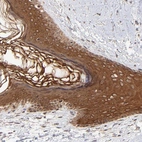

Immunohistochemical staining of human skin shows cytoplasmic positivity in epidermal cells.